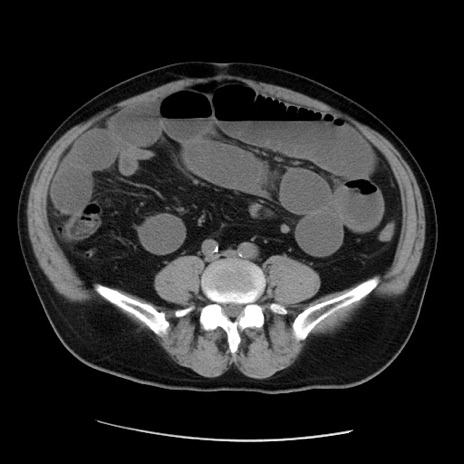

症例20(横断像)

【症例】 60歳代男性

【主訴】 腹部膨満、嘔吐

【現病歴】5日前頃より倦怠感を認め食事量減少し4日前の朝嘔吐、食事摂取困難となった。 3日前近医受診し点滴施行され整腸剤などを処方された。 当日他院を受診し、腹部膨満著明、炎症反応の上昇(CRP10.8、WBC11200)あり、紹介受診となる。

【身体所見】 意識JCS1 受け答えがはっきりしないBP 111/57mHg、 P 67bpm、、BT35.2°C、SpO2 97%(RA)、 腹部:膨隆、打診で鼓音あり、全体的に圧痛有り、腸蠕動音(-)、反跳痛ははっきりせず。

【データ】WBC 11400、CRP 14.20